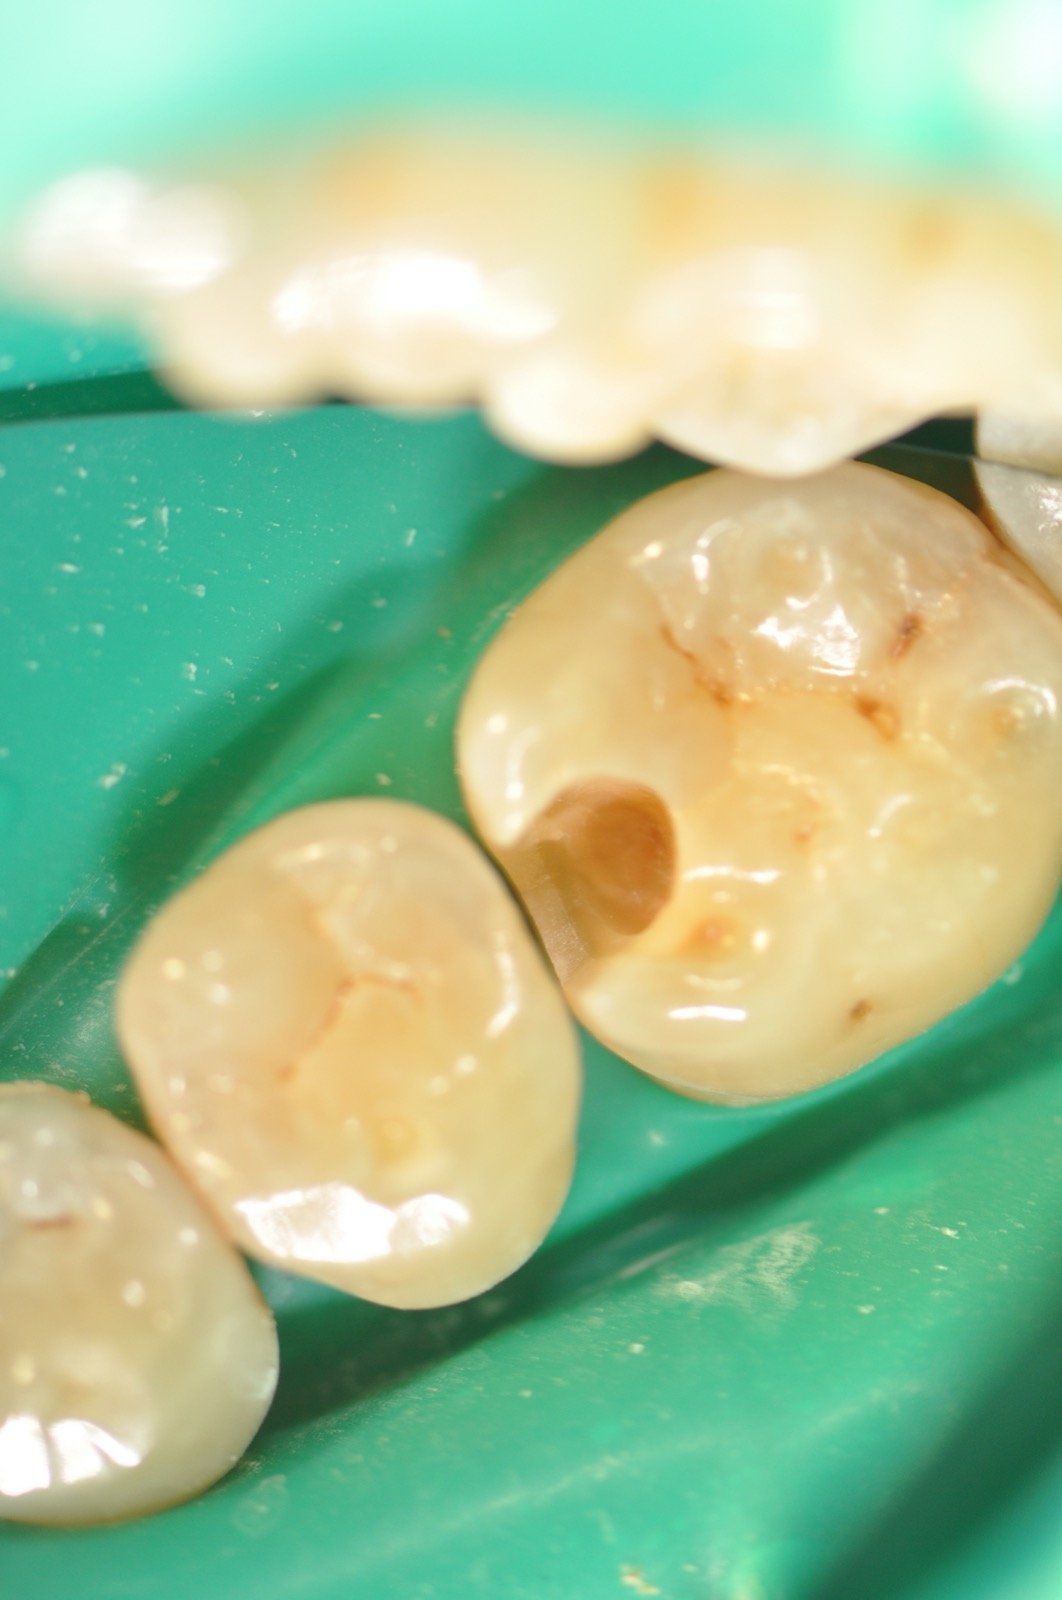

Odontoiatria conservativa

La conservativa è una branca dell'odontoiatria restaurativa che ha come scopo quello di “conservare” l’elemento dentario. Ciò significa che si cercherà, in un dente non eccessivamente compromesso, di evitare la devitalizzazione ove possibile e di restaurare il dente secondo protocolli rigidi che ci garantiscano una longevità della ricostruzione.

Andremo ad effettuare il restauro del dente nella sola parte compromessa dalla carie salvaguardando la sostanza biologica residua, da noi giudicata sana, in modo tale da garantire una ricostruzione di qualità.